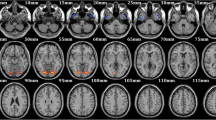

Compared with controls, FLE patients showed significantly decrease gray matter in bilateral putamen and right caudate (p < 0.05, FWE corrected). The results are showed in Table 2 and Fig. 1.

Compared with controls, FLE patients revealed significant increased and decreased Fx → y (outflow) from the right caudate (seed region) to inferior frontal gyrus-triangular and from bilateral putamen (seed regions) to right middle frontal gyrus and frontal gyrus medial-orbital, respectively, as shown in Fig. 2 A. Also, significant increased and decreased Fy → x (inflow) from left calcarine to right caudate and from left cerebellum_6/vermis_6 to bilateral putamen, respectively as shown in Fig. 2 B. Table 3 shows the tmaps information of both seed and voxel including their cluster sizes.

Causal connectivity differences between FLE and Healthy controls. a Outflow: Caudate_R (seed) to Frontal_inf_tri_L, Putamen_L (seed) to Frontal_mid_R and Putamen_R (seed) to Frontal_mid_orb_R; (b) Inflow: Caudate_R (seed) to Calcarine_L, Putamen_L (seed) to Cerebelum_6_L and Putamen_R (seed) to Vermis_6. p < 0.05, FWE corrected